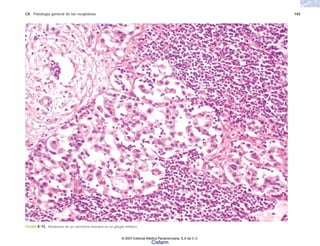

El término patología (proviene del griego πατηοσ, en-

fermedad, y λογοσ, conocimiento) significa “el estudio